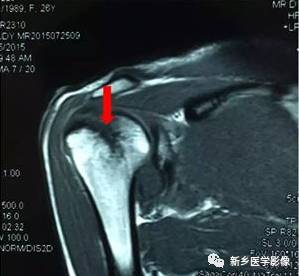

病例四:

红色箭头:肩胛下肌腱损伤

黄色箭头:肱二头肌长头腱(在位)